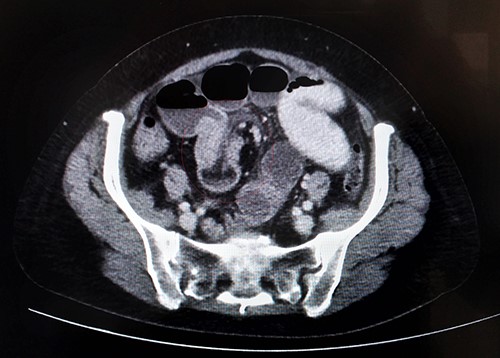

She had clinical features consistent with a sub-acute small bowel obstruction; so an urgent abdominal computed tomography (CT) scan was obtained. We inserted a wide bore nasogastric (NG) tube and commenced intravenous (IV) fluids. The CT scan reported small bowel obstruction due to ileo-ileal intussusception in its distal two-third segment (Fig. 2). After adequate resuscitation and detailed informed consent, she was brought to theatre for a laparoscopy-assisted small bowel resection. There was a 20-cm-long ileo-ileal intussusception with a lead point suggestive of a tumour-like growth (Figs 3–5). The tumour-like growth was a 30 × 25 × 20 mm polypoid mass arising from the bowel mucosa. Segmental ileal resection and stapled side to side primary anastomosis was done. She recovered well and went home 4 days later. A completion CT thorax was unremarkable. The histopathology returned as inflammatory myofibroblastic tumour (IMT) associated with intussusception of the small bowel (R0 resection). The case was discussed at our GI multidisciplinary meeting (MDM), a second histopathological opinion and surveillance CT thorax, abdomen and pelvis (TAP) in 6 months was recommended. She was followed up in clinic, developed a mild superficial surgical site infection (SSI) of the midline abdominal wound managed conservatively with regular dressings only, and later healed successfully by secondary intention. She was followed up in the clinic 6 months later, remained well and healthy to date and surveillance CT TAP did not show any metastasis or recurrence. The second pathological opinion concluded that the lesion is actually an IFP.

Axial section of abdominal CT scan showing bowel within bowel configuration with a layering effect indicating the site of ileal intussusception.

Although CT scan is up to 100% accurate in detecting a bowel intussusception [15], an IFP is usually not detected preoperatively probably because of the rare nature of the lesion itself, non-specific symptoms and difficult visualization within the involved bowel segment. Even if an endoluminal growth or mass is imaged preoperatively, it is commonly missed due to lack of distinctive radiological features on routine CT scans [12]. CT features of an intussusception include bull’s eye, target or sausage-shaped double-ringed lesions [15]. A bowel within bowel configuration is also suggestive of an intussusception [9]. Due to lack of a definite preoperative diagnosis, most cases are diagnosed after surgical exploration. The exact surgical treatment is controversial; however, most commonly employed treatment is segmental resection of the involved segment of bowel with sufficient margins to cater the possibility of a malignant lesion.